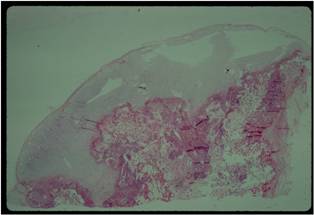

Pathology:

- Medullary and cortical continuity w/ underlying bone

- Hyaline Cartilage Cap with lobular growth

Gross Pathology

- The osteochondroma is completely covered in periosteum

- Cut surface shows hyaline composition of cartilage cap

Cap

- Younger patients thicker cap because of growth hormone

- Smooth or knobby

- 2 mm to 1 cm thick

Beneath the cap, calcified cartilage which appear as white deposits are present

Microscopic Pathology